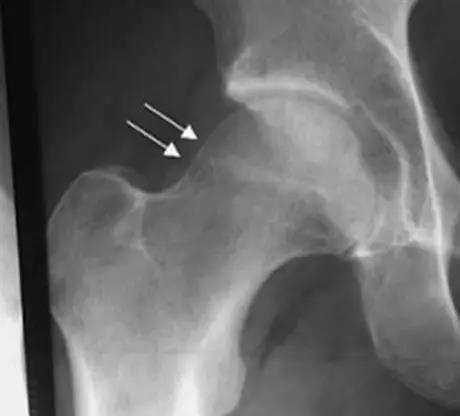

凸轮撞击型FAI▼

- 股骨头颈间的凹陷不足,伴局部的骨质增生。

- 股骨头颈的“ 枪柄样” 畸形。

- 股骨头颈联合处前上缘骨性突起。

- 非圆形的股骨头。

- 股骨头颈联合处前缘骨性突起、骨质硬化,α角增大。